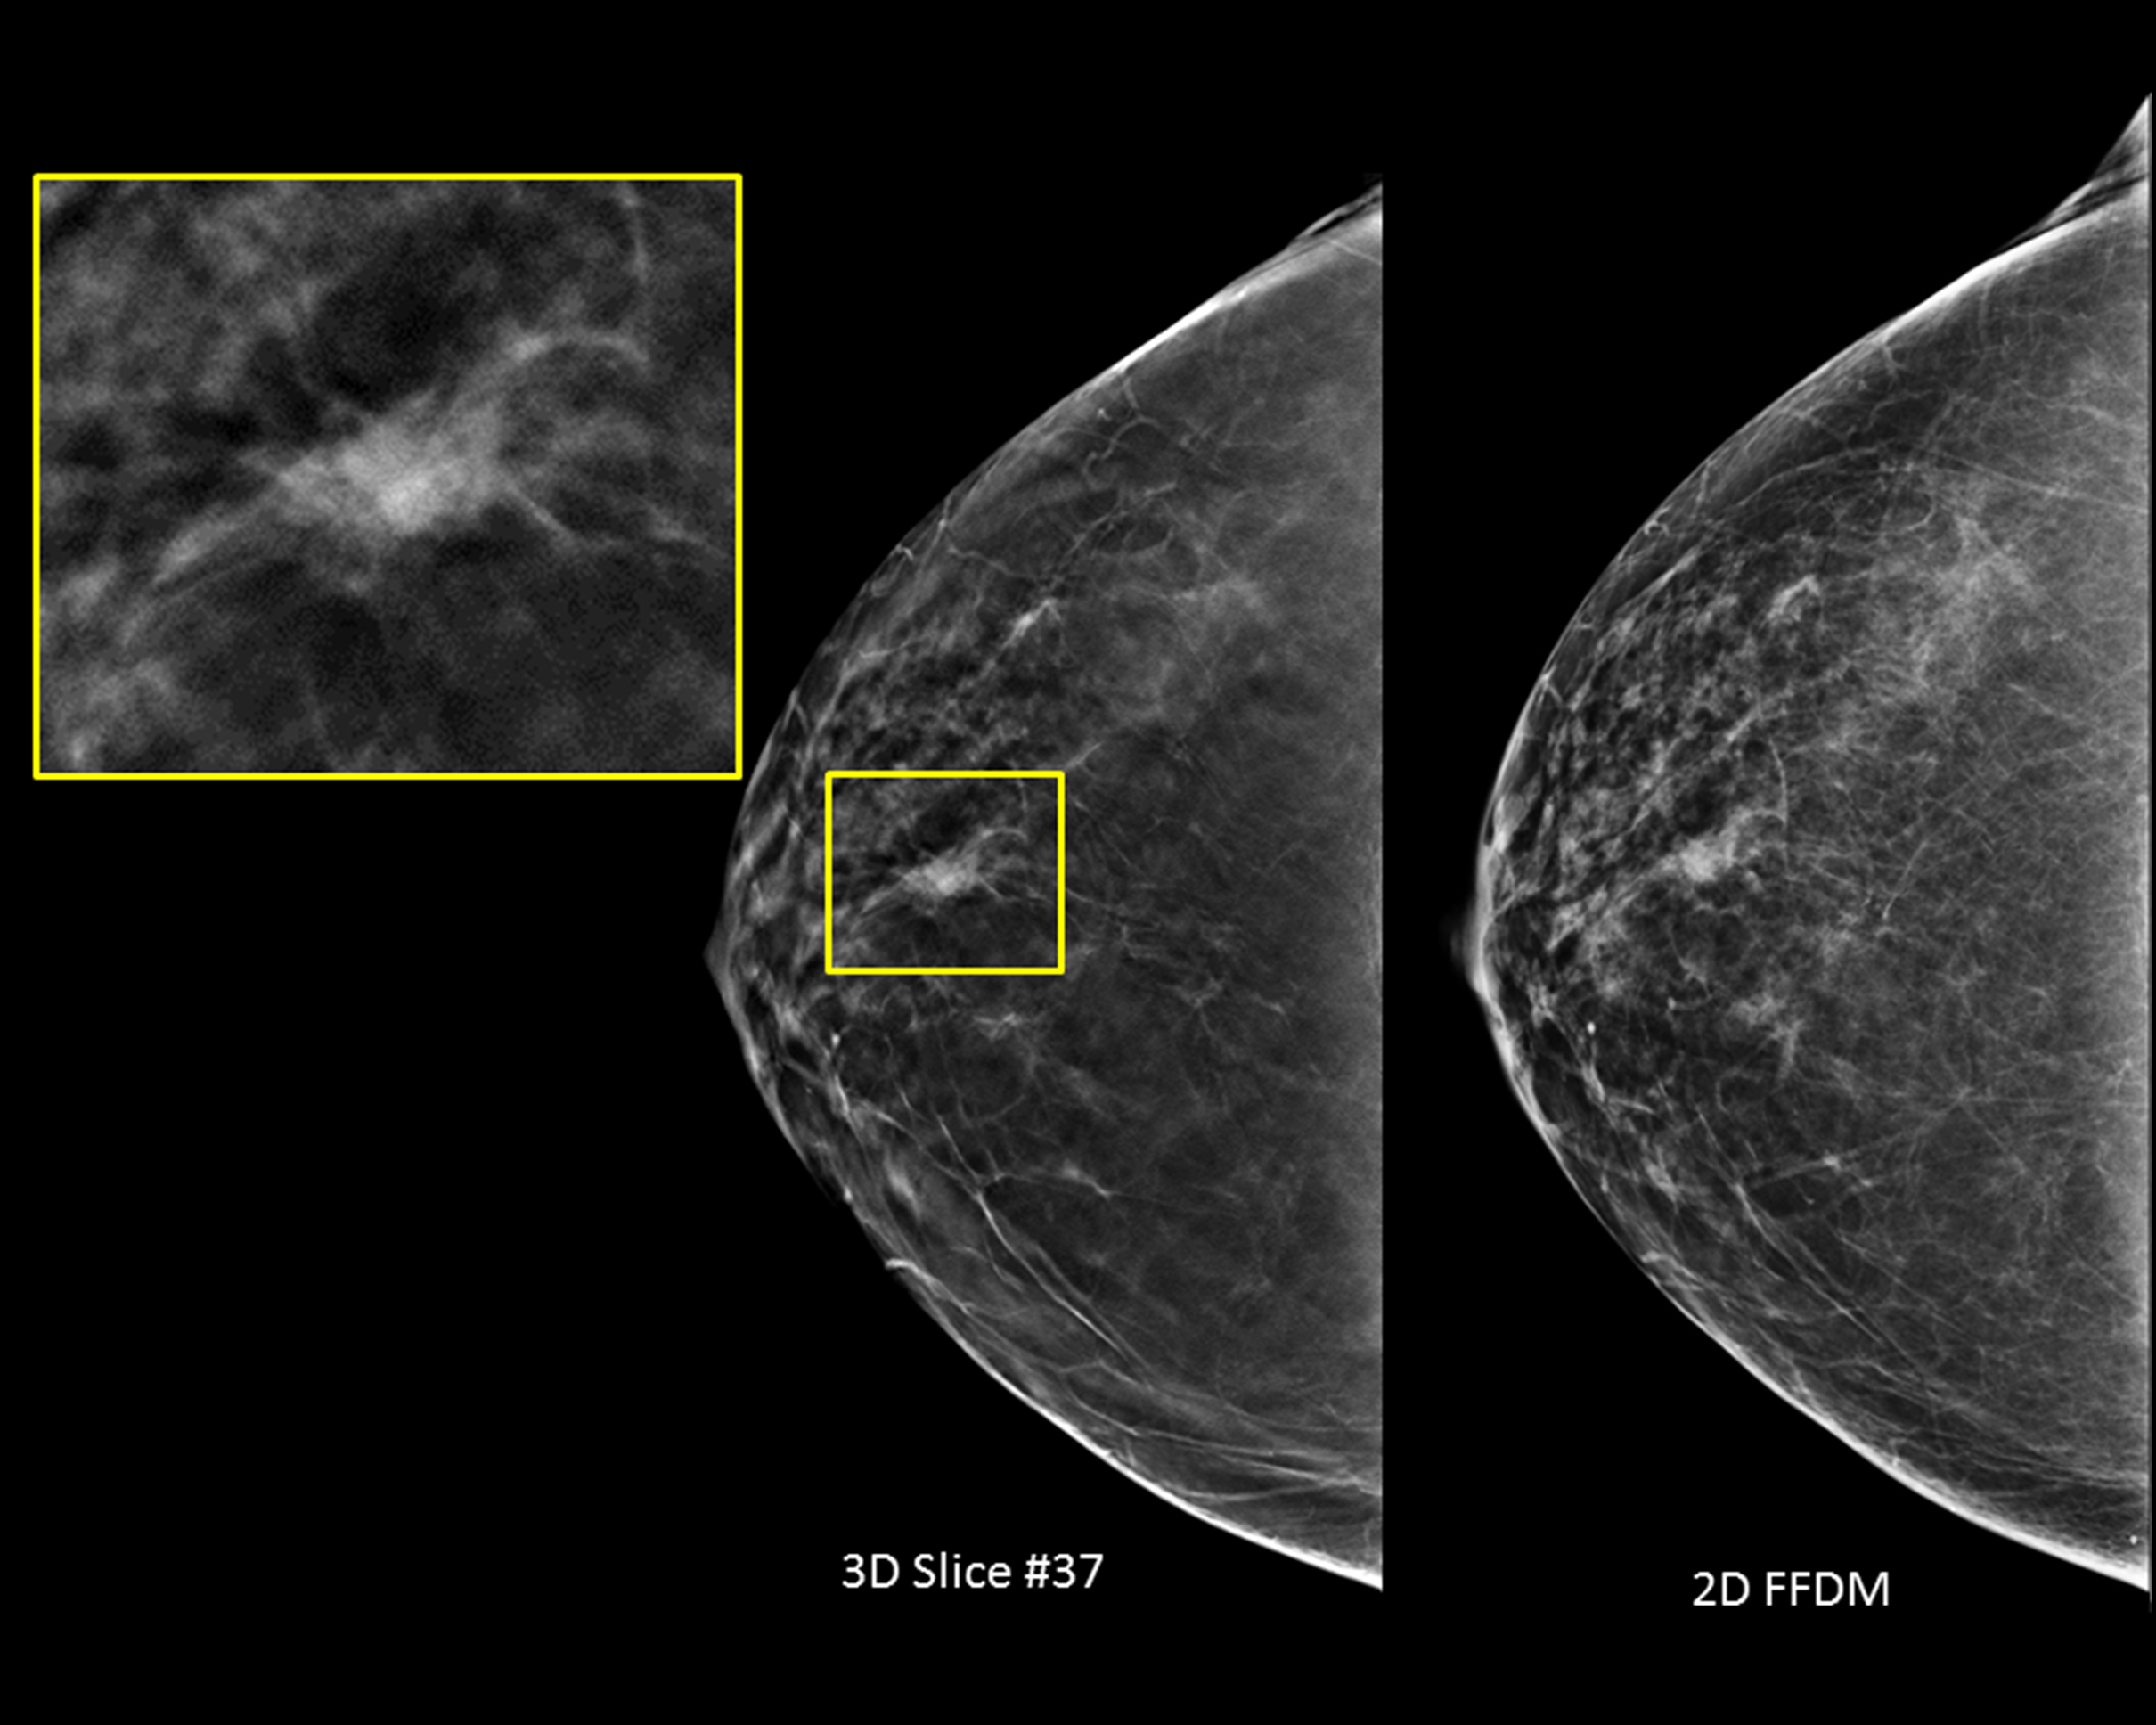

Маммограмма кальцинаты визуализируются

Маммография и ее роль в диагностике фиброаденомы молочной железы

Маммография - это рентгенологическое исследование молочных желез. Оно позволяет выявить различные изменения в тканях, включая фиброаденому. На маммограммах можно увидеть структурные особенности опухоли и отследить ее динамику во времени.